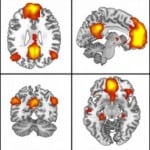

Understanding Our Brains at Rest to Help Treat Alzheimer’s

July 8, 2013

Breakthroughs in cognitive neuroscience: Highlighting influential research from the past 20 years This series will explore influential papers in cognitive neuroscience, as measured by the number of times they are cited each year. The papers featured are a sampling of many important works in the field over the past 20 […]